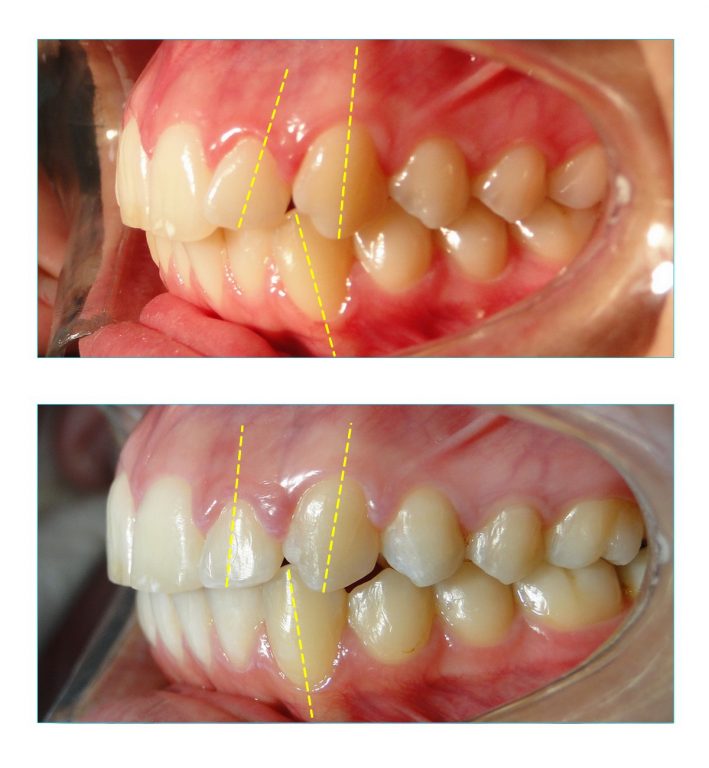

Nas fotografias laterais podemos observar o eixo de alguns dentes em tracejado amarelo e o quanto estes foram desinclinados durante o tratamento ortodôntico, que foi feito com aparelho de porcelana.